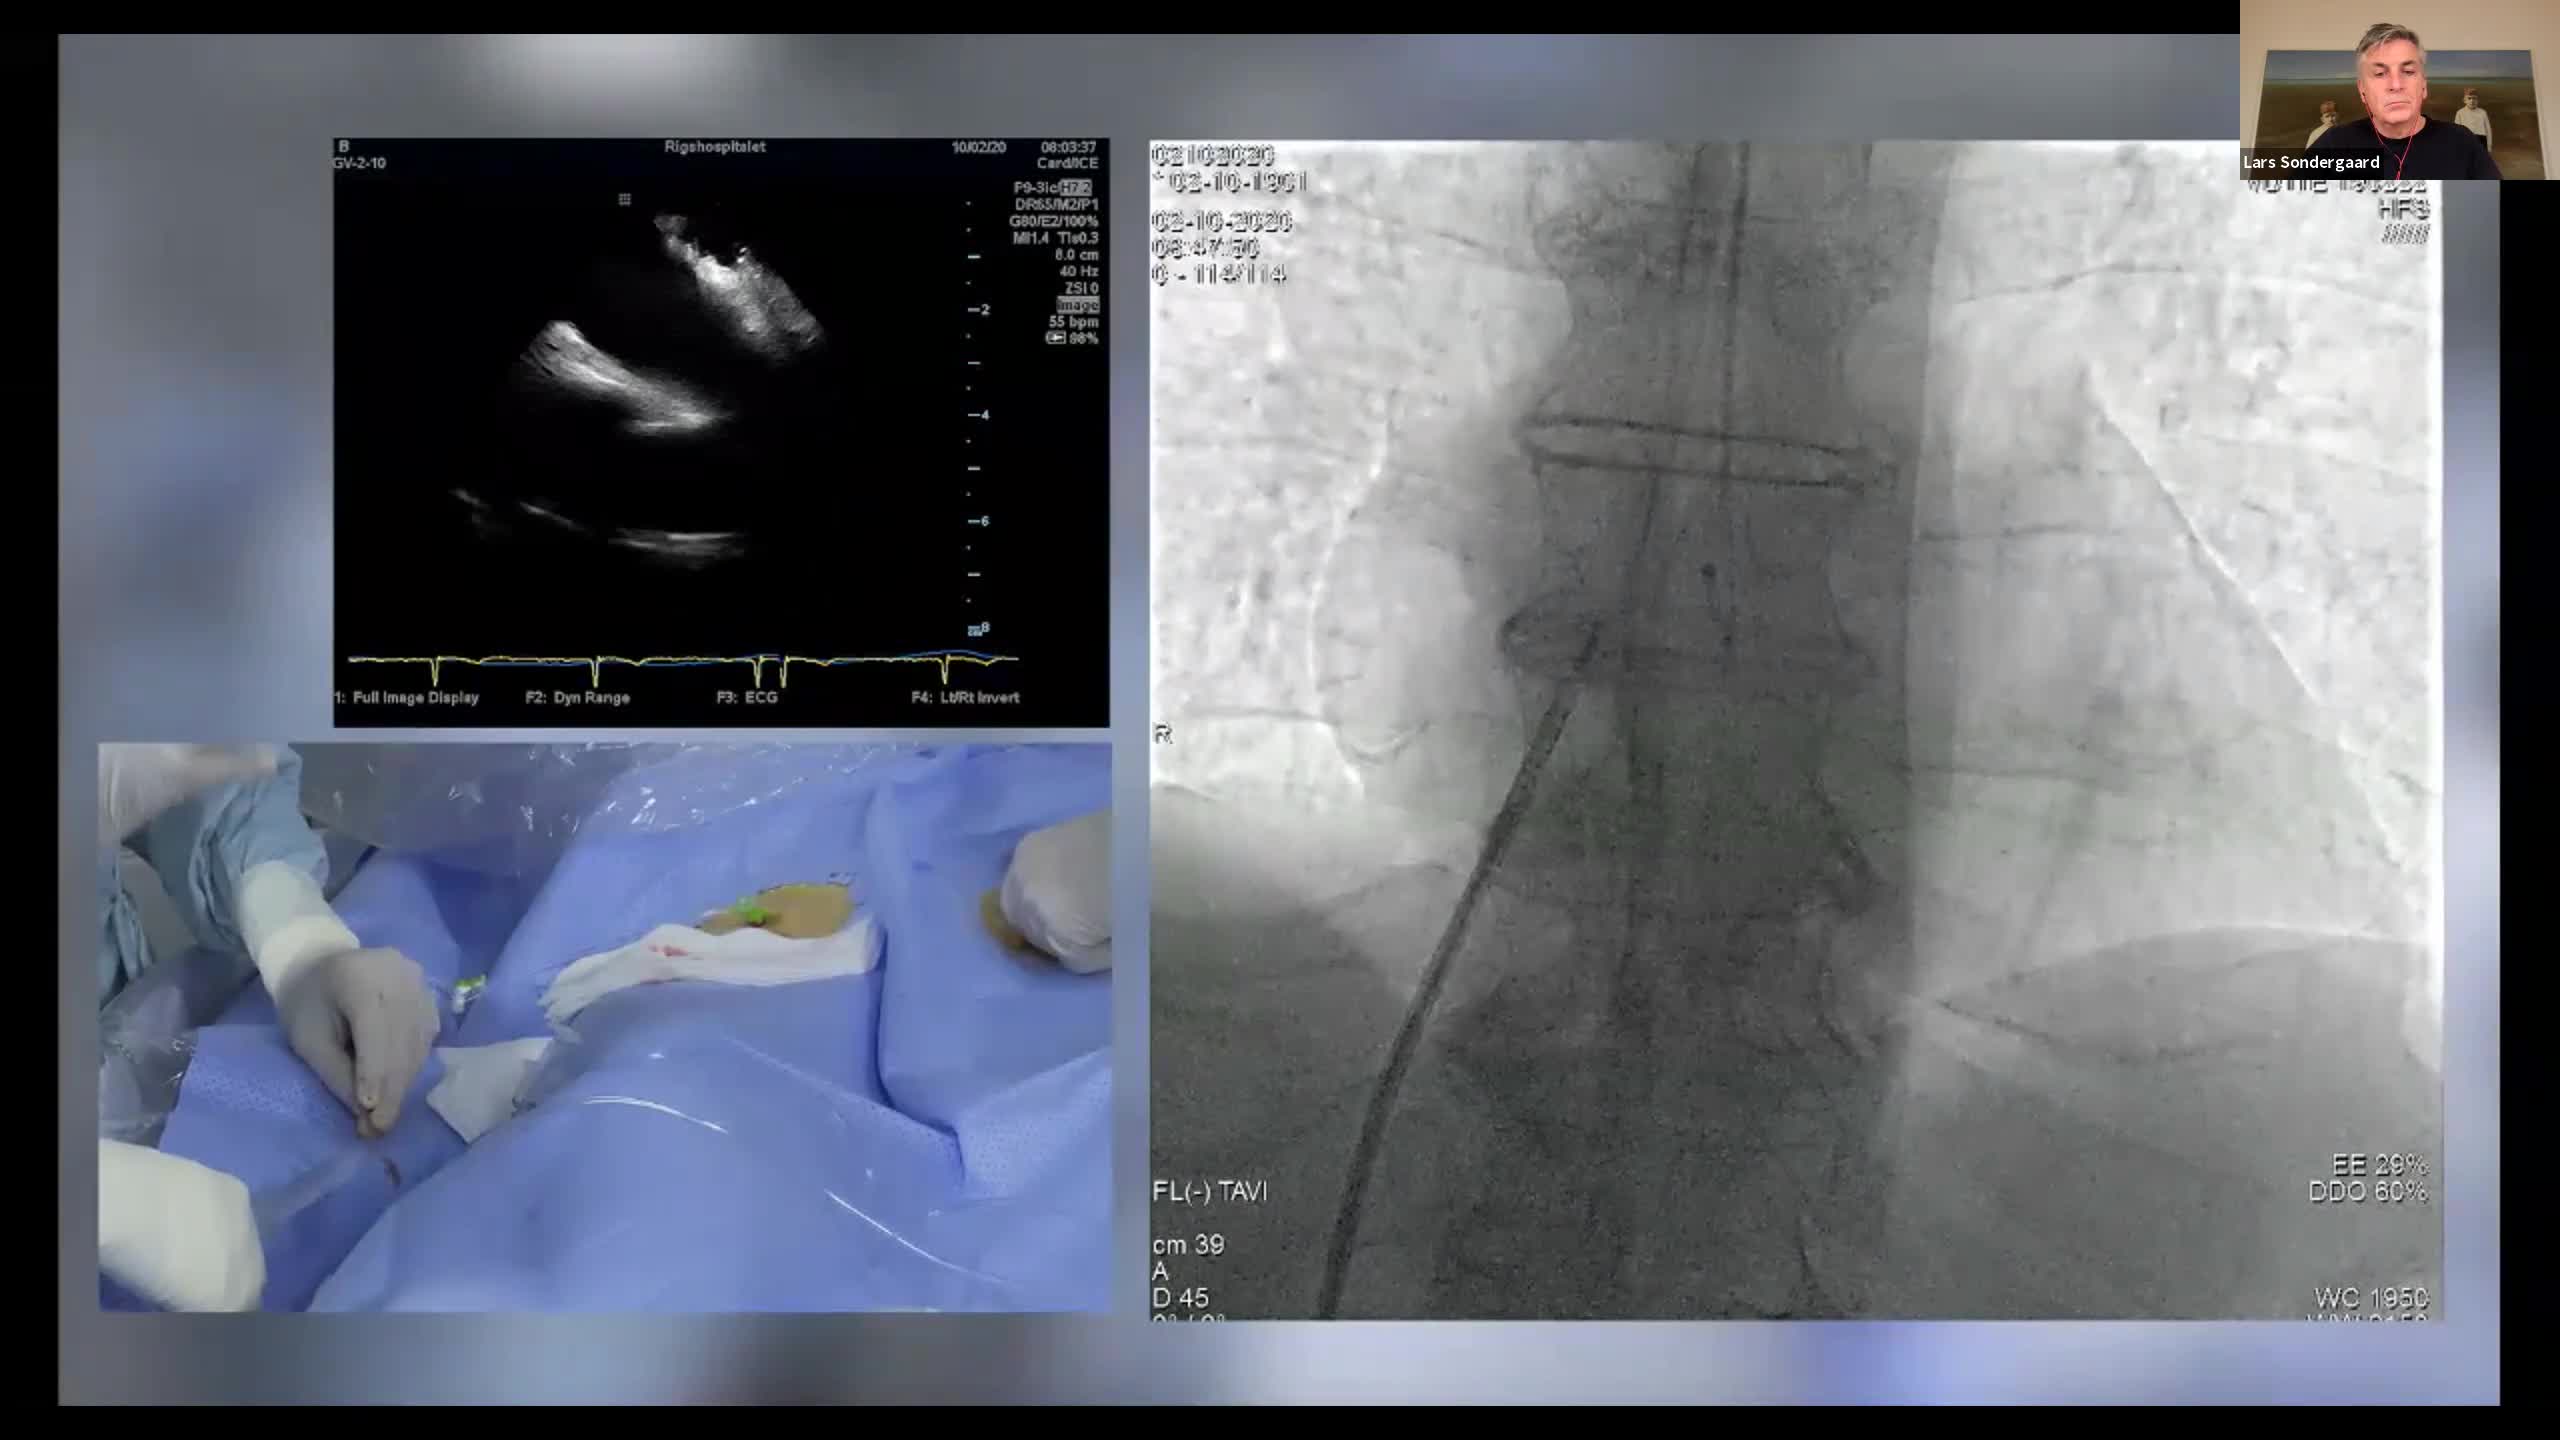

CSI CATHLAB LIVE - INTER-ATRIAL SHUNT FOR DECOMPRESSION OF THE LEFT ATRIUM IN A PATIENT WITH VERY SEVERE HEART FAILURE WITH THE AFR DEVICE